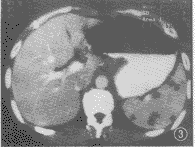

图3,4 CT增强。脾脏肿大,脾内见多发低密度无强化灶,CT值为50 HU左右,边界清楚,大小均在20 mm以内